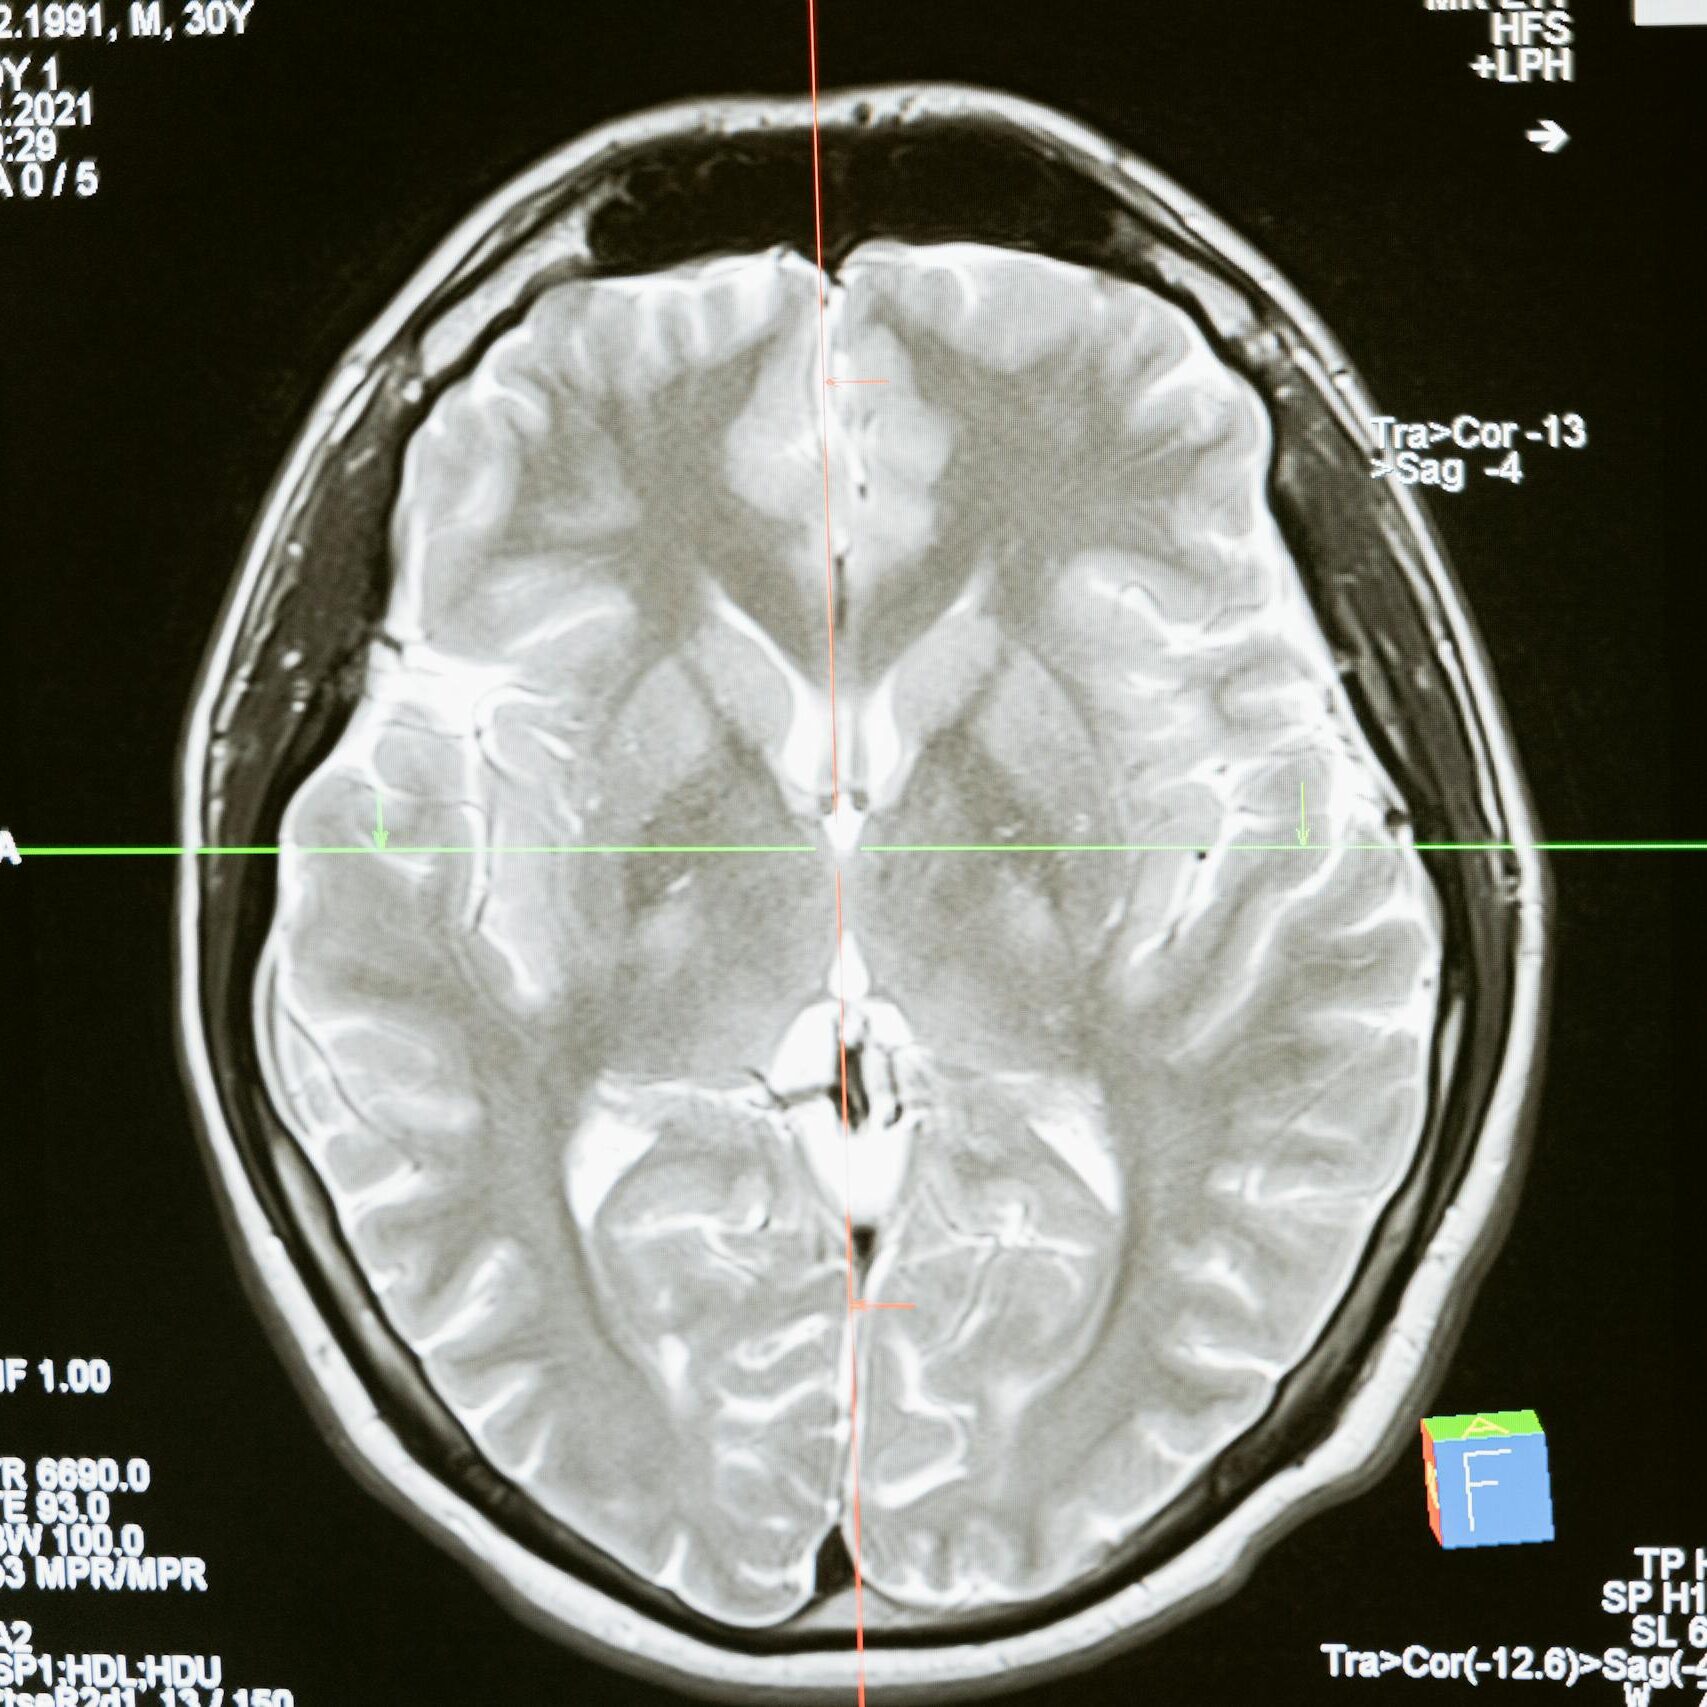

Meningioma is a type of brain tumor that develops in the membranes (meninges) surrounding the brain and spinal cord. Most meningiomas are considered benign, but they can still grow large enough to press on the brain or spinal cord, leading to serious neurological problems.

Because meningiomas often develop slowly, they may not be diagnosed until symptoms become significant and imaging such as MRI or CT scans is performed. Treatment can include surgery, radiation therapy, or, in some cases, ongoing monitoring.